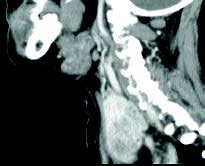

Mujer de 46 años que consulta por disfonía desde hace 2 meses, no fumadora, con antecedentes de hipertensión arterial y colesterol alto. En la exploración con fibroscopia naso-laríngea se aprecia parálisis de cuerda vocal izquierda. Como protocolo de las parálisis recurrenciales se pide TAC cérvico-torácico, para valorar el trayecto del nervio recurrente laríngeo, donde no se observan lesiones en mediastino o pulmón. Se aprecia gran crecimiento de la glándula tiroidea con lesiones quísticas y nodulares más intensas en lóbulo tiroideo izquierdo: bocio multinodular.